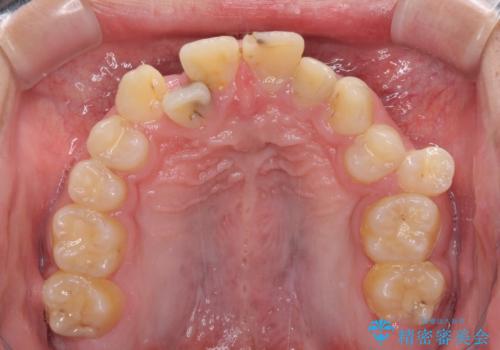

- むし歯が多く、歯並びも悪いとのことで、以前通院されていたご家族の紹介で来院された患者様です。

口腔内に無頓着であったため、まずはしっかりと歯磨きトレーニングを行い、必要な虫歯治療を行いました。

矯正治療は、むし歯が酷く抜歯が望ましい歯を1本抜歯して、ワイヤー装置にて整えることとしました。